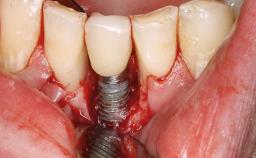

Recurrent Peri-implantitis Leading to Implant Removal

A 65-year-old female patient was referred to the periodontist for assessment and management of implant site 12. Implant 12 had been placed ten years previously and restored with a cemented single crown. The patient was a non-smoker in good general and periodontal health. On examination there were 7 mm probing depths at implant 12 with suppuration and bleeding on probing. The patient was aware of the presence of pus but had no discomfort. A periapical radiograph showed marginal bone loss to approximately the third thread of the implant. Previous radiographs obtained from the referring clinician indicated that there had been progressive bone loss since the implant was restored. A diagnosis of periimplantitis was made.